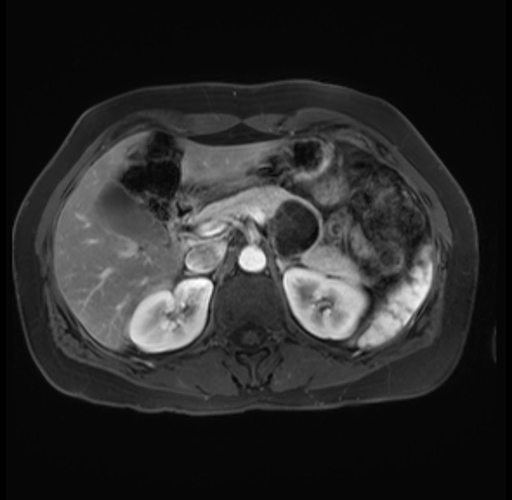

Imaging Analysis

Look through the patient's CT scan to identify any areas of concern for the necessary procedure.

Based on your CT findings, which issue(s) are present and would give reason for "planned slowing down moment(s)" in this case?

Considering a standard distal pancreatectomy procedure, what step(s) of the operation would you do differently in this case?